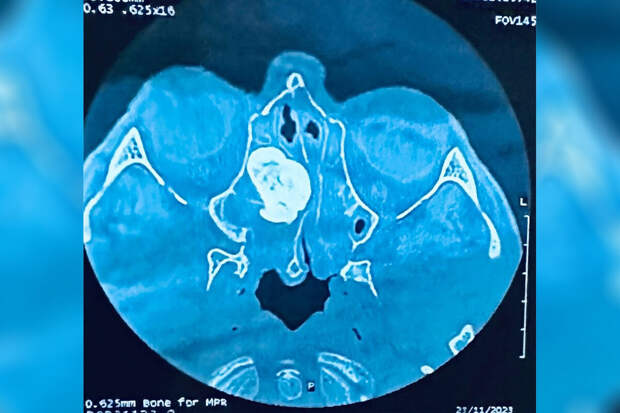

В ходе обследования в носовых пазухах пациента была обнаружена доброкачественная опухоль большого размера.Остеома блокировала соустья с пазухами носа, препятствуя оттоку слизи и аэрации пазух. Было принято решение о проведении малоинвазивной операции, без единого разреза медики удалили новообразование. Спустя несколько дней пациента выписали на амбулаторное лечение.